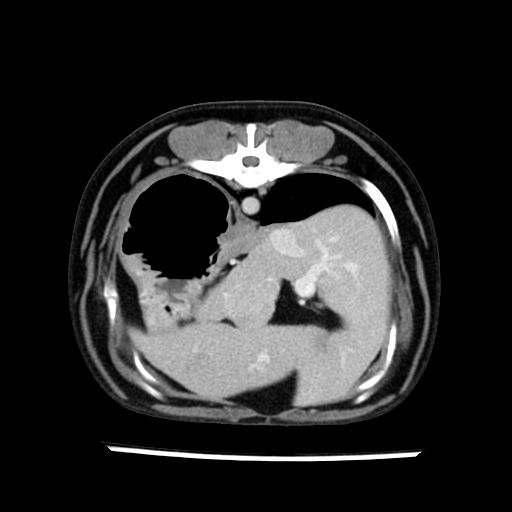

prescritto esame TAC

sequenza immagini limitata al fegato reni e surreni

le immagini ecografiche rispetto alla tac datano circa 7 mesi prima ,le surrenali sono normali nonostante il test acth sia risultato positivo .all’esame TAC dopo diversi mesi risultano aumentate armonicamente nel volume e si individua un forte sospetto di adenoma ipofisario .

sospetto adenoma ipofisario vs. meno probabilmente meningioma della base; intertiziopatia polmonare; lesione espansiva epatica, verosimilmente del lobo laterale sinistro, di sospetta natura neoplastica; lesioni spleniche di natura da definire; iperplasia/ipertrofia delle ghiandole surrenali, bilateralmente; vertebra di transizione del rachide toracico; tenosinovite cronica del muscolo bicipite brachiale di destra.